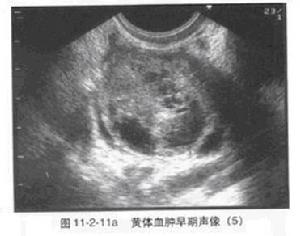

卵巢黃素瘤儀器檢測成熟濾泡在排卵後,即形成黃體。在血管形成期,血液流入黃體腔內(黃體血腫),故在正常狀態下,黃體即為囊性,在病理情況下,若其直徑為1.5--2.5cm,稱囊性黃體;超過2.5cm則稱黃體囊腫素瘤。

A.粒層黃體囊腫囊腫素瘤:此種最為常見,來自黃體的血腫,可發生於育齡期。直徑2.5-6cm不等,最大可達11cm;大於4cm的少見,囊腫向卵巢表面突起,早期可似血腫,卵巢表面呈紅褐色,內為透明或褐色漿液,囊壁淺黃色,呈特徵性花環狀。

在B超的表現為雙側或單側卵巢囊性增大、囊壁光滑、囊內反射呈均勻無回聲區,或有分隔或小網狀結構。孕早期發現可於孕中期消失,亦可發現後一直保持有大小,經B超監測後一般可明確良性診斷。臨床也有極少數孕期增大,出現腹水,囊內液為淡血性的嚴重卵巢黃素瘤報導。